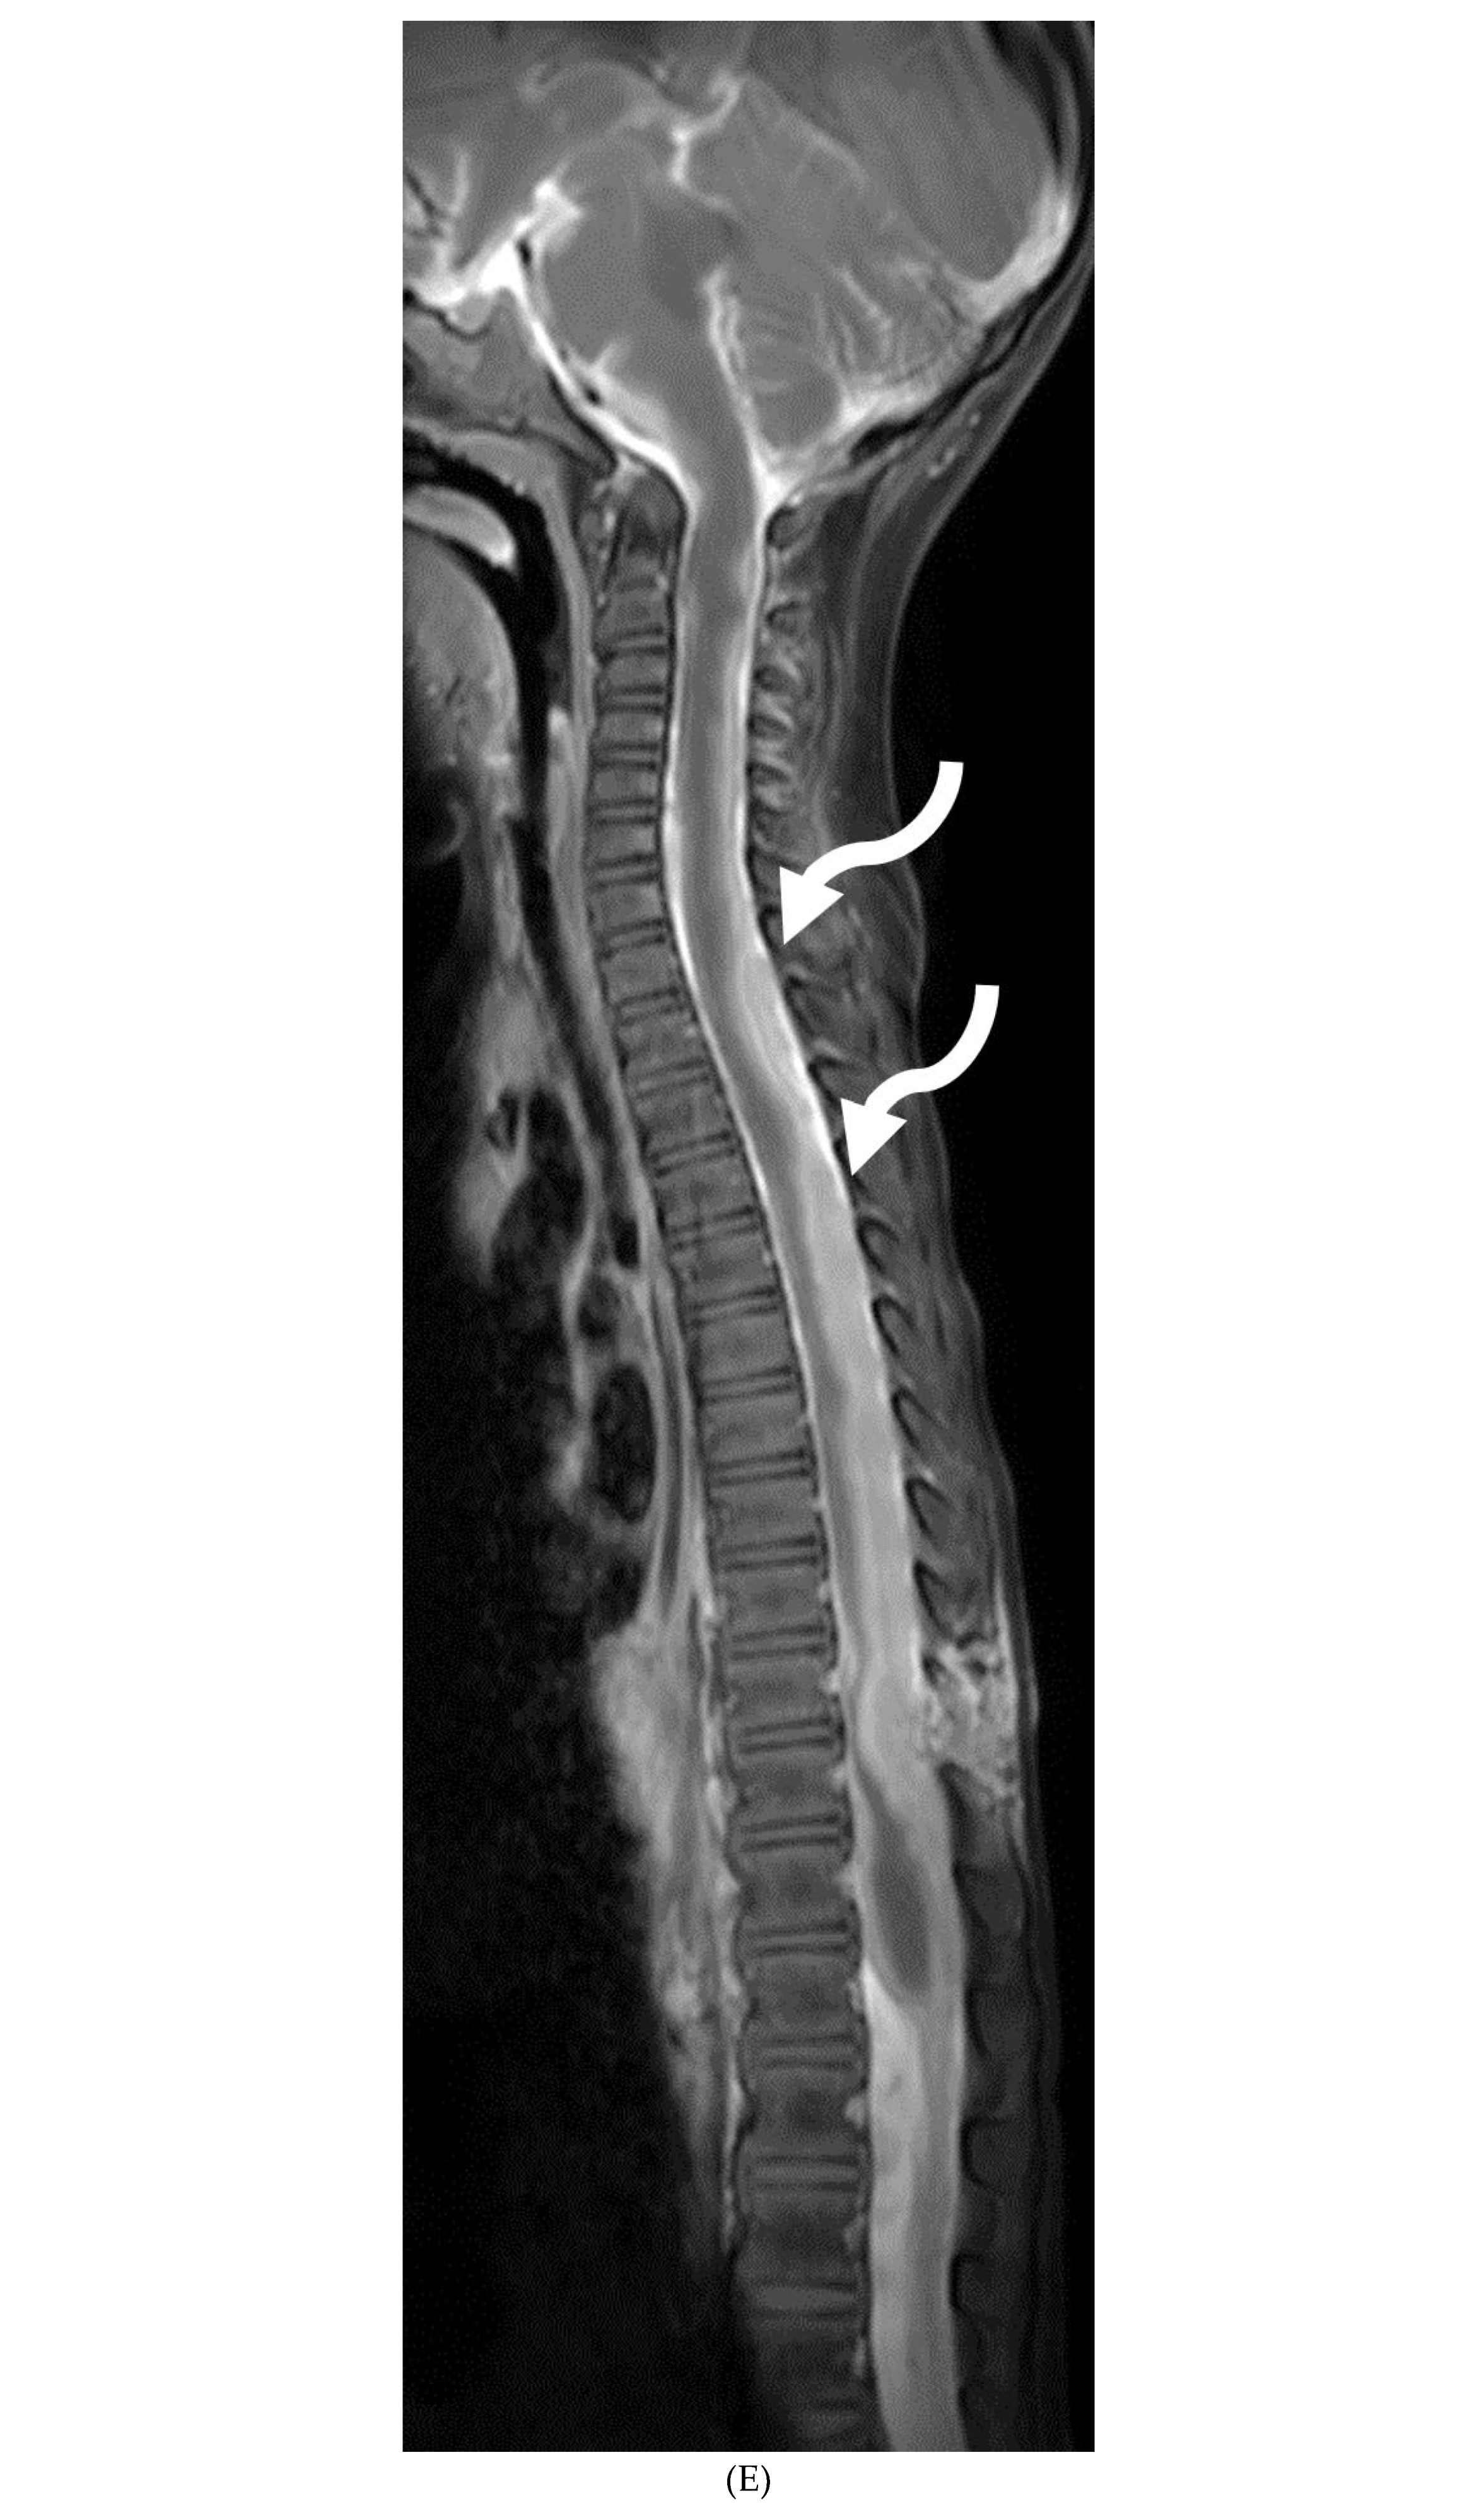

GUILLAIN BARRE SYNDROME

- Alkan O, Yildirim T, Tokmak N, Tan M. Spinal MRI findings of guillain-barré syndrome. J Radiol Case Rep. 2009;3(3):25-8. Epub 2009 Mar 1. PMID: 22470650; PMCID: PMC3303301. [CrossRef]

- Zuccoli G, Panigrahy A, Bailey A, Fitz C. Redefining the Guillain-Barré spectrum in children: neuroimaging findings of cranial nerve involvement. AJNR Am J Neuroradiol. 2011 Apr;32(4):639-42. Epub 2011 Feb 3. PMID: 21292802; PMCID: PMC7965877. [CrossRef]

- Yikilmaz A, Doganay S, Gumus H, Per H, Kumandas S, Coskun A. Magnetic resonance imaging of childhood Guillain-Barre syndrome. Childs Nerv Syst. 2010 Aug;26(8):1103-8. Epub 2010 Jun 17. PMID: 20556395. [CrossRef]

- Byun WM, Park WK, Park BH, Ahn SH, Hwang MS, Chang JC. Guillain-Barré syndrome: MR imaging findings of the spine in eight patients. Radiology. 1998 Jul;208(1):137-41. PMID: 9646804. [CrossRef]